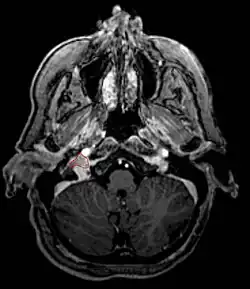

Glomus Jugulare

- Commonly arise from the paraganglia of the jugular bulb

- Typically invade the tympanic cavity and jugular foramen

- Can extensively invade petroclival region

- Can invade cavernous sinus above

- Can invade hypoglossal canal below

- Clinical presentation typically with tinnitus or hearing loss, but may also impact jugular foramen CNs